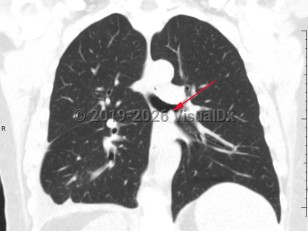

Imaging Studies image of Bronchial carcinoid tumor - imageId=7903592. Click to open in gallery.  caption: '<span>Coronal CT image demonstrates a  soft tissue density nodule within the left mainstem bronchus.  Bronchoscopic biopsy was consistent with endobronchial carcinoid.</span>'

Coronal CT image demonstrates a soft tissue density nodule within the left mainstem bronchus. Bronchoscopic biopsy was consistent with endobronchial carcinoid.